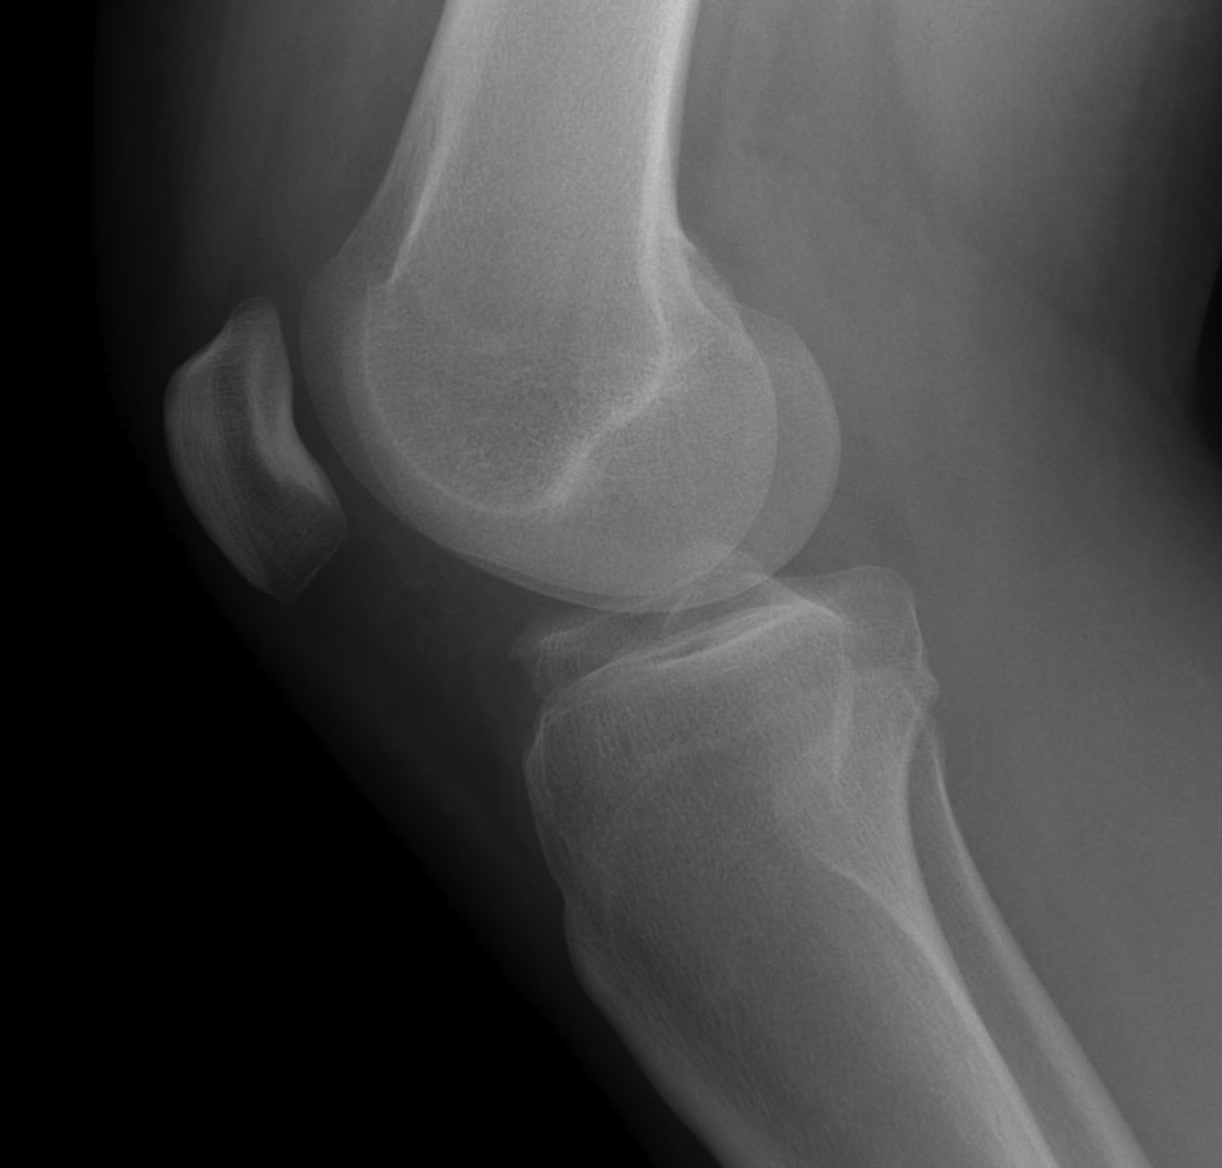

X-ray

Usually normal

Segond Fracture

- small avulsion fracture of lateral proxima tibia

- is sign of lateral capsular avulsion

- pathognomonic of ACL tear

Tibial avulsion

- more common in children

- can be seen in adults